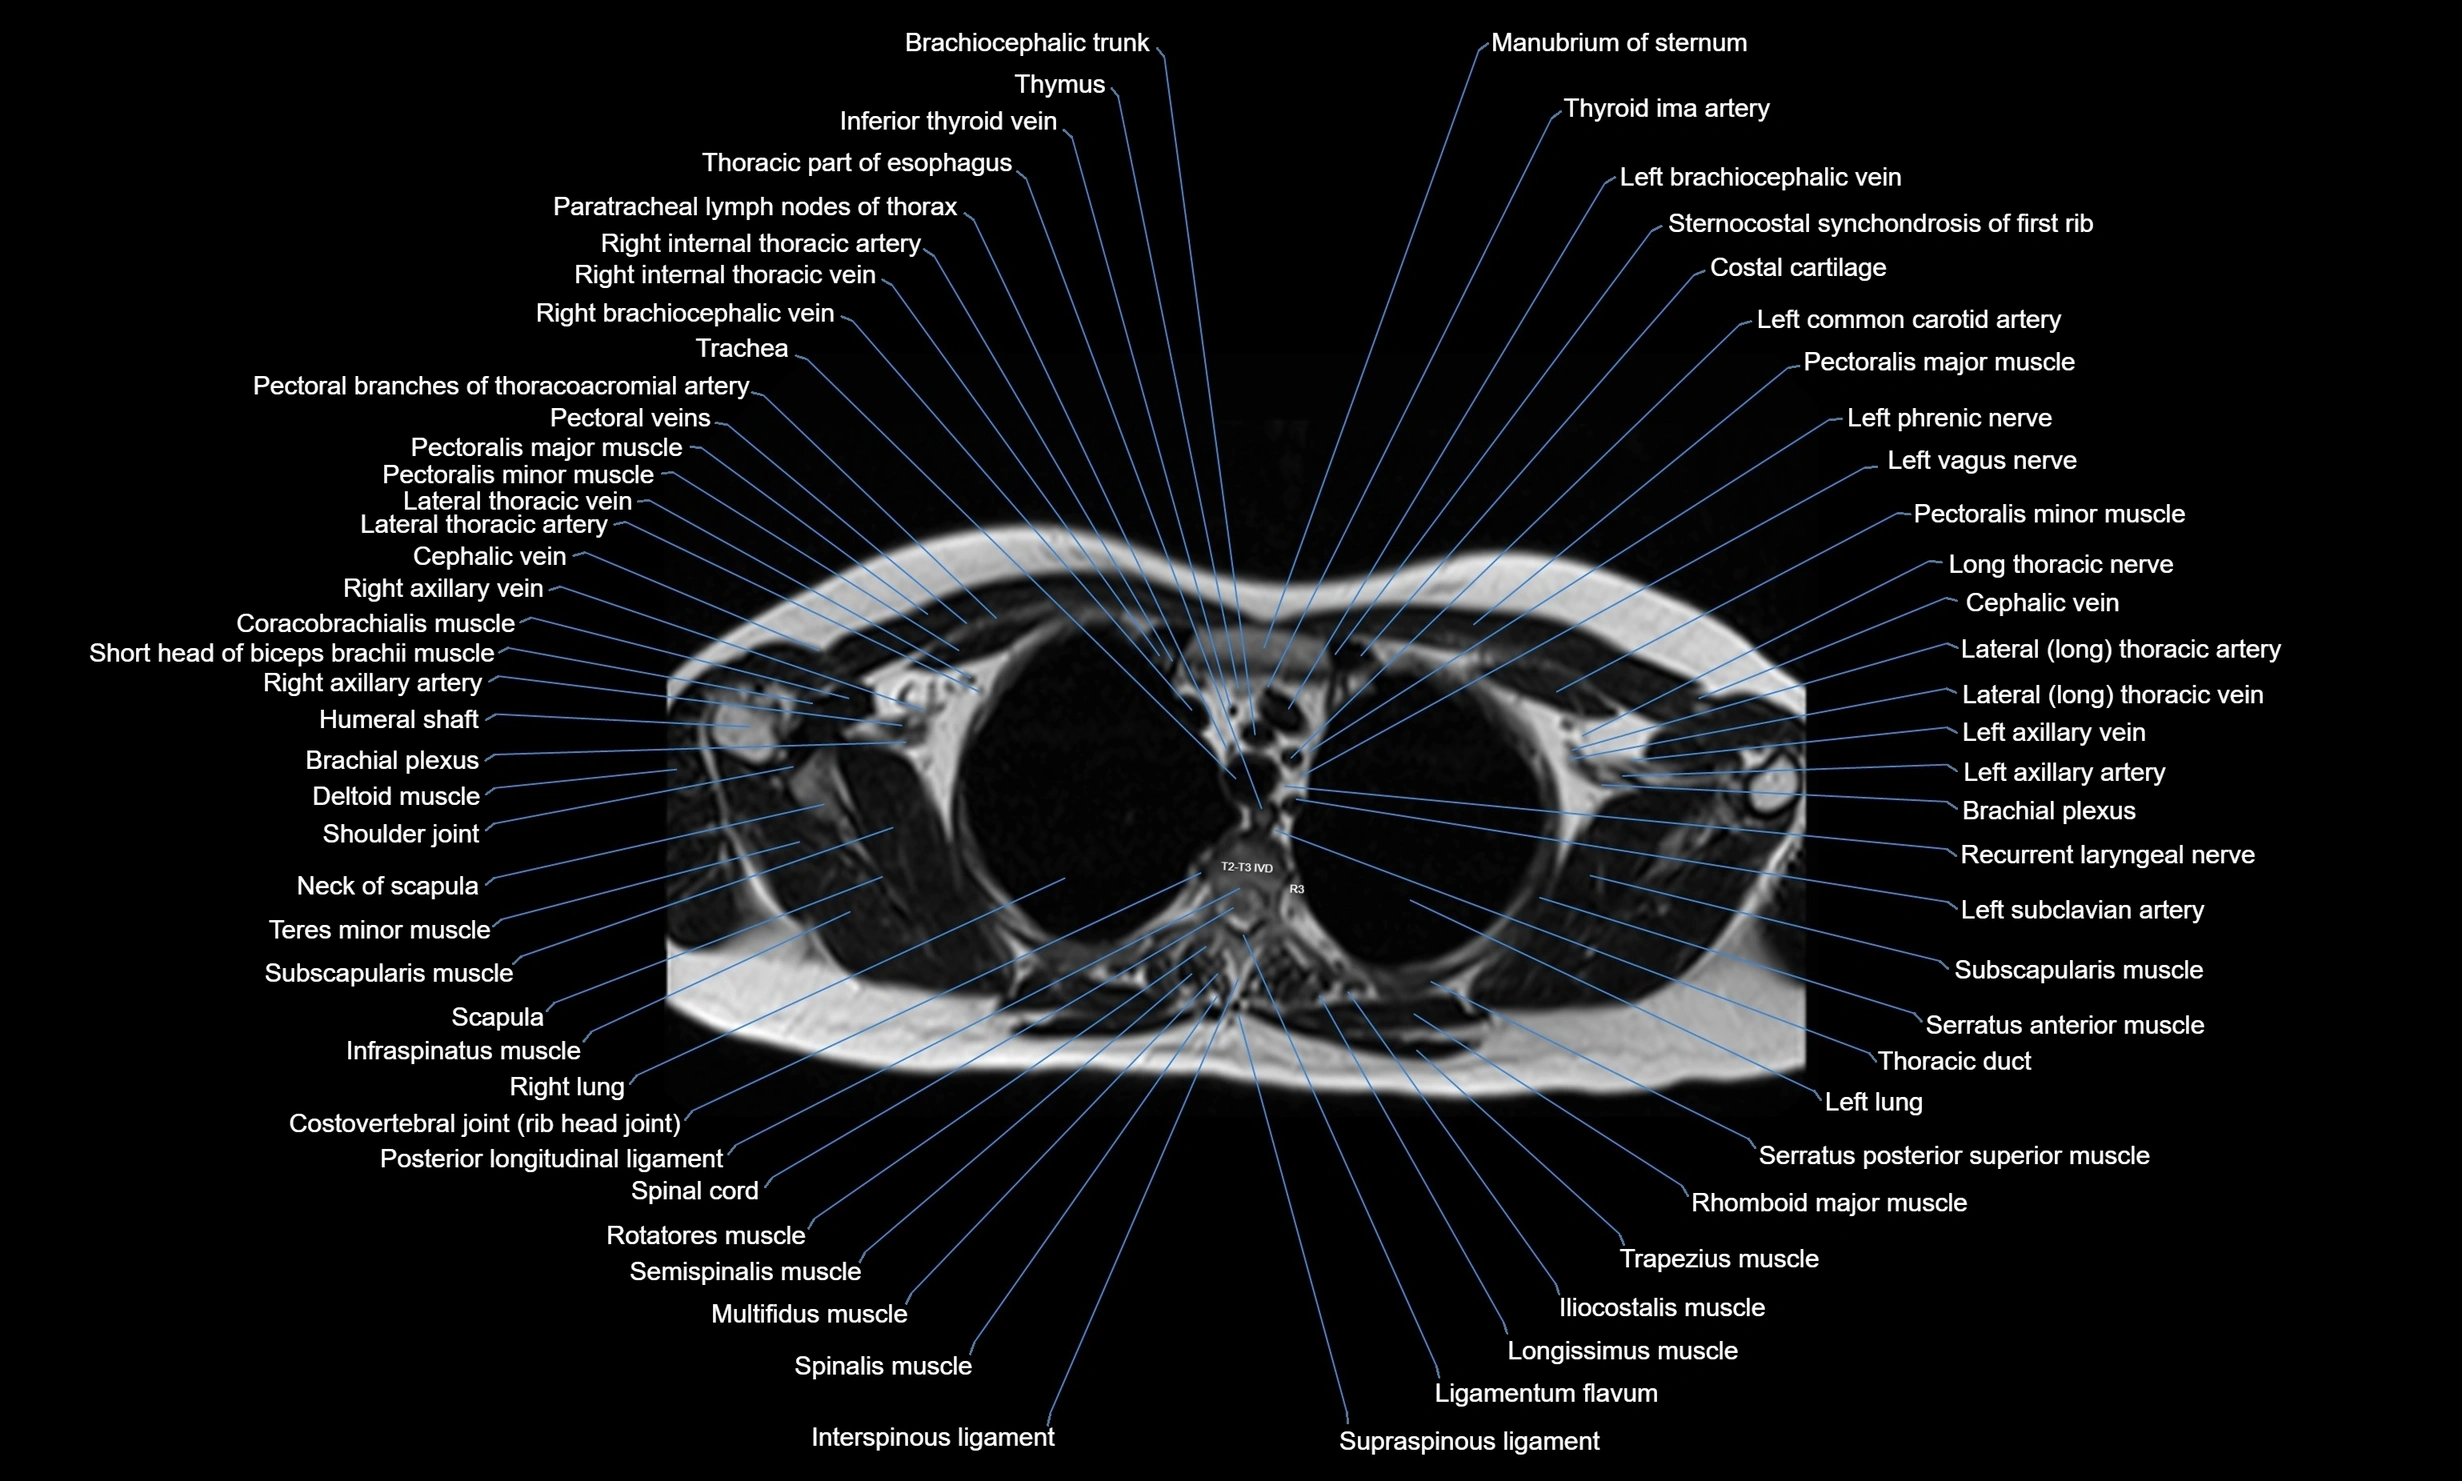

MRI images